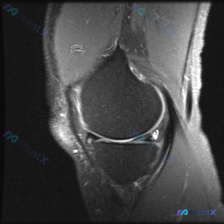

刚看到一份膝关节MRI单矢状位切面的读片需求,核心问题是观察半月板异常,我整理了完整的分析思路分享给大家。 一、病例基本影像信息 这是一张膝关节矢状位MRI影像,根据信号特征判断:不符合典型T1加权像(骨髓信号偏低,关节软骨、积液呈高信号),更符合质子密度加权像(PDWI)或T2加权像,这类序列对半...